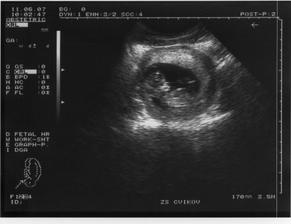

13.9. jsem dělala první testík a málem jsem přehlédla tu slabounkou čárku. Byl to menší šok, jelikož se o miminko už rok snažíme. Následující den jsem udělala další testík pro potvrzení a z nevolnosti už mi bylo více než jasné, že bude čárka silnější-a také že ano. První utz. 25.9. - 5+2tt mimi má 17mm. Druhý utz. 18.10. - 9+1tt mimi má 23,3mm. Třetí utz. 6.11. - 11+2tt. Čtvrtý utz. 29.11 - 14+4tt Malé má 16 cm. 16tt-16+3tt jsem přibrala 2 kila a začínám se pěkně cpát.Na utz. s námi byla nastávající babička. 20tt jsem zatím přibrala 4.5 kg. 21 tt další utz., váha 59kg. To s námi byl na utz. i tatínek. Začínající váha byla 53kg. 25tt kontrolní utz. 61kg. Miminko je zatím stále zadečkem dole.Tak máme 36tt, miminko už je otočené hlavičkou dole a já mám 65,5 kg. Přecházíme k doktorovi do nemocnice a čekáme kdy se prcek rozhodne přijít mezi nás, podle pana doktora to má být ještě před termínem 🙂